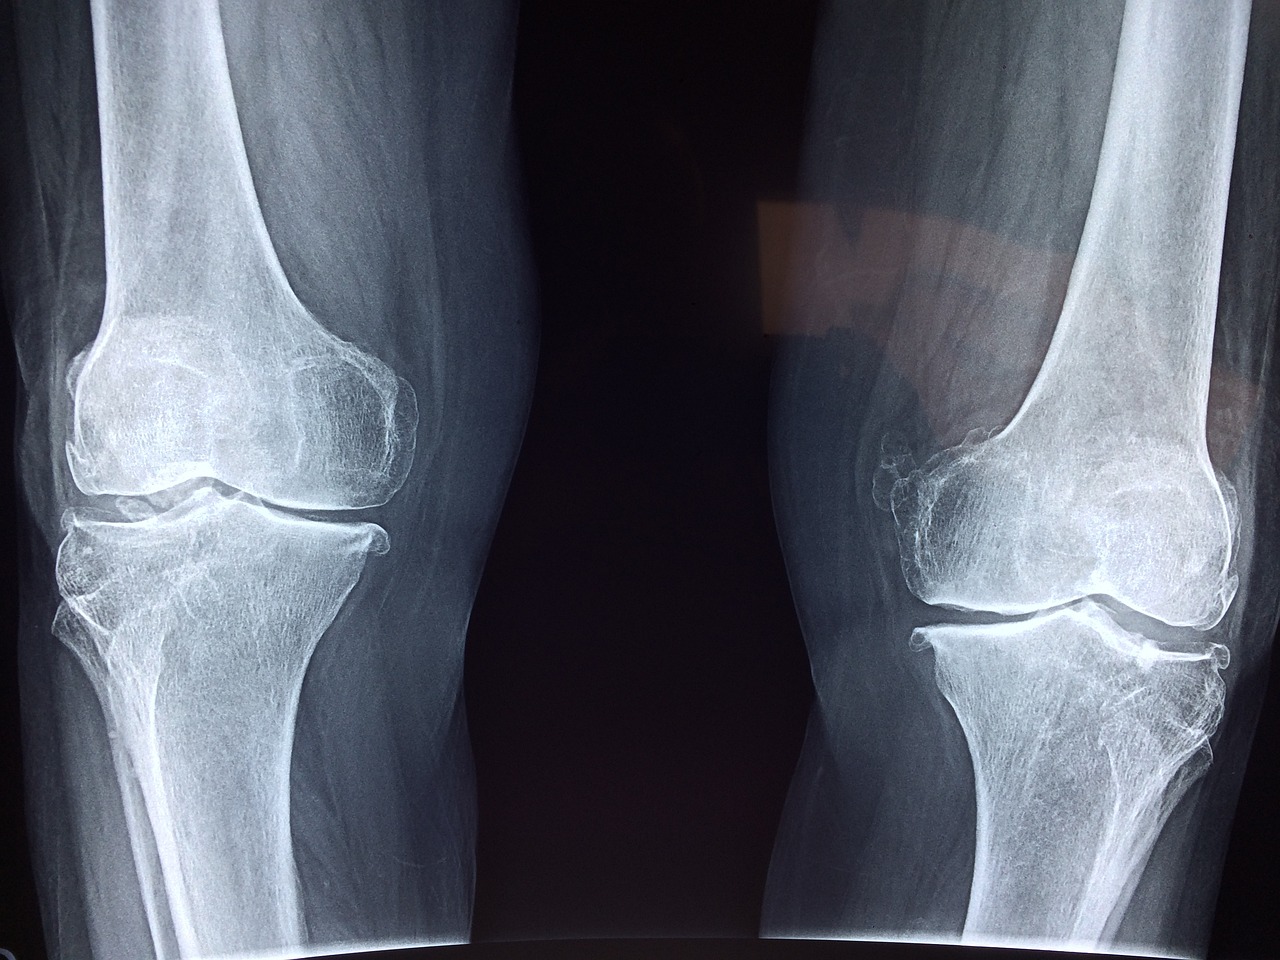

나이가 들수록 무릎관절은 다양한 원인으로 손상되기가 쉽습니다. 무릎의 손상정도가 작다면 약물, 주사, 물리치료 등 보존적 요법으로 치료가 가능하지만 만약 무릎의 손상정도가 강하고 보존적 치료가 어렵고 환자가 일상생활에서의 어려움을 느낄정도로 고통스럽다면 무릎 인공관절 수술을 고려하는 것이 좋습니다. 무릎인공관절수술은 말 그대로 손상된 무릎관절을 제거하고 그 자리를 인공관절(무릎) 기구로 대체하는 수술입니다. 그렇기 때문에 통증을 야기하는 문제 부위를 제거하기 때문에 통증의 근본적인 원인을 해결한다는 점에서 통증을 없애는 가장 확실한 치료방법입니다.